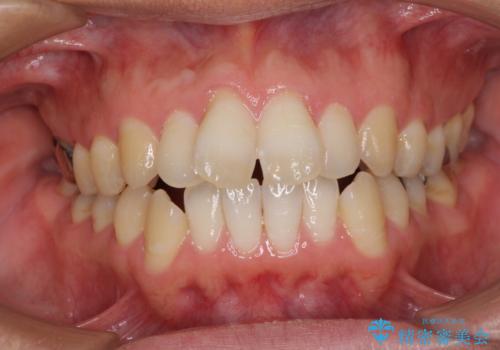

- 前歯のデコボコと、上顎前歯の突出感を気にして来院された患者様です。

通常の咬み合わせ位置と比較して、上顎の歯列が全体的に前方にある状態で、上下前歯の前後方向の位置に著しい差がありました。